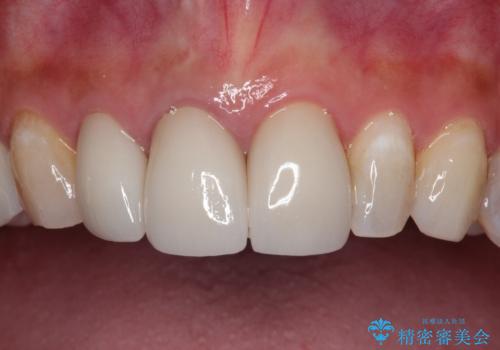

歯並びの改善とインプラントでのかみ合わせの回復 インプラント・セラミック・矯正全顎治療

- 歯医者が怖くて悪い歯をそのままにしてしまった、悪いところを治したいとのことで来院されました。

虫歯の歯や、歯を抜いてしまったところをそのまま放置していたことにより、歯並びも悪くなっていました。

矯正をはじめ、根の治療・インプラント・セラミックによる全体治療を提案させていただき、治療をしていくこととなりました。